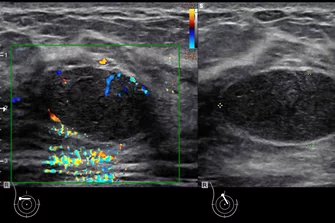

Sonographie - Point of Care Ultraschall

„Point-of-Care Ultraschall“ ist ein weiter gefasster Begriff, der viele Szenarien umfasst, in denen tragbare Ultraschallgeräte eingesetzt werden können. Ein Patient kann zum Beispiel mithilfe eines tragbaren Ultraschallgeräts im Krankenwagen gescannt werden, während er sich auf dem Weg in die Notaufnahme befindet. Oder ein Patient kann im Traumaraum gescannt werden, nachdem er in die Notaufnahme des Krankenhauses eingeliefert wurde. Der Begriff „Point-of-Care Ultraschall“ weist also darauf hin, dass ein transportables Ultraschallgerät überall dorthin gebracht werden kann, wo sich der Patient befindet.

Genauso kann das tragbare Gerät in der Praxis, bei Hausbesuchen oder im Krankenhaus eingesetzt werden.